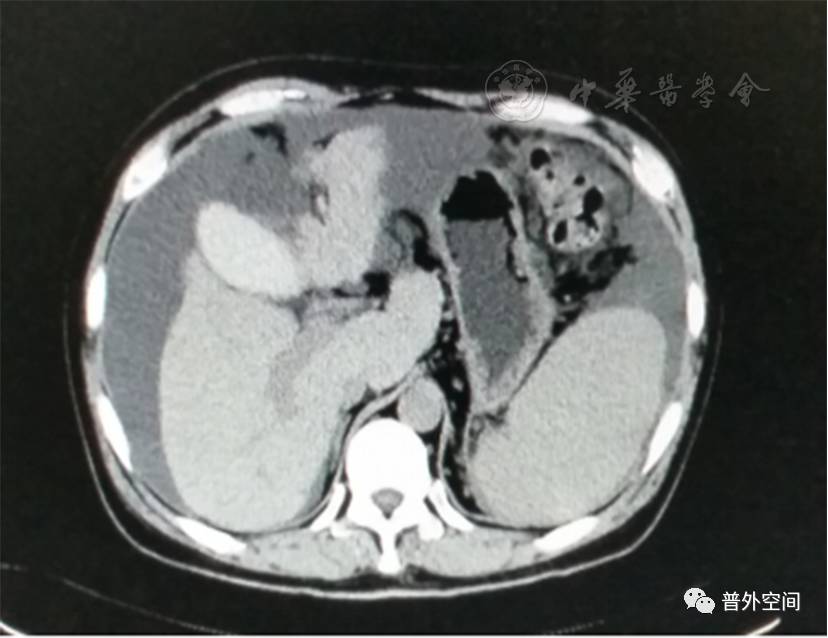

我们将这种方法应用到100多例没有艾滋病病毒感染的一般肝硬化患者身上,结果收到更好的疗效。例如1例男性患者,56岁,失代偿期肝硬化大量腹水合并脐疝(见封四,图1)。CT检查提示肝脏明显萎缩,肝脏体积1 302 ml,大量腹水,脾脏肿大(见封四,图2)。在多家医院就诊后都认为需要做肝移植。我们对患者进行脾切除加脐疝修补,自体骨髓经门静脉输注治疗。手术后3个月,肝功能Child-Pugh分级从C级转成*级A**,手术后1年,肝功能正常,腹部伤口愈合良好(见封四,图3)。CT检查提示肝脏明显增大,体积1 796 ml,腹水基本消失(见封四,图4)。针对肝功能C级的患者手术风险比较高,围手术期输注白蛋白、凝血酶原复合物、纤维蛋白原,改善肝脏功能,手术中经胃网膜右静脉插管埋置骨髓输注装置,输注自体骨髓。随着自体骨髓干细胞在肝内发生复杂的变化,肝硬化组织中的胶原纤维被降解和吸收,肝脏组织的增生和体积增大,肝功能好转,门静脉压力会逐渐降低。但是在手术后1年内,仍然有可能随时发生上消化道出血,需要经胃镜检查,套扎食管黏膜下明显曲张的静脉血管。这样我们做脾脏切除解除脾功能亢进,不做贲门周围血管离断,减少了手术损伤。食管黏膜下静脉曲张用胃镜下套扎治疗。待肝硬化逐渐逆转,食管黏膜下静脉曲张程度将会逐渐减轻。

图2 手术前腹部CT断层照片